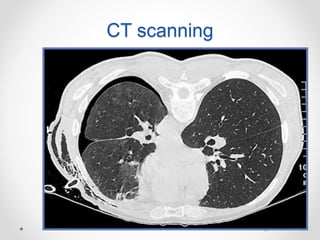

CT scanning

 It is recommended in difficult cases such as

patients in whom the lungs are obscured by

overlying surgical emphysema

 To differentiate a pneumothorax from suspected

bulla in complex cystic lung disease

CT can diagnose easily

pneumothroax